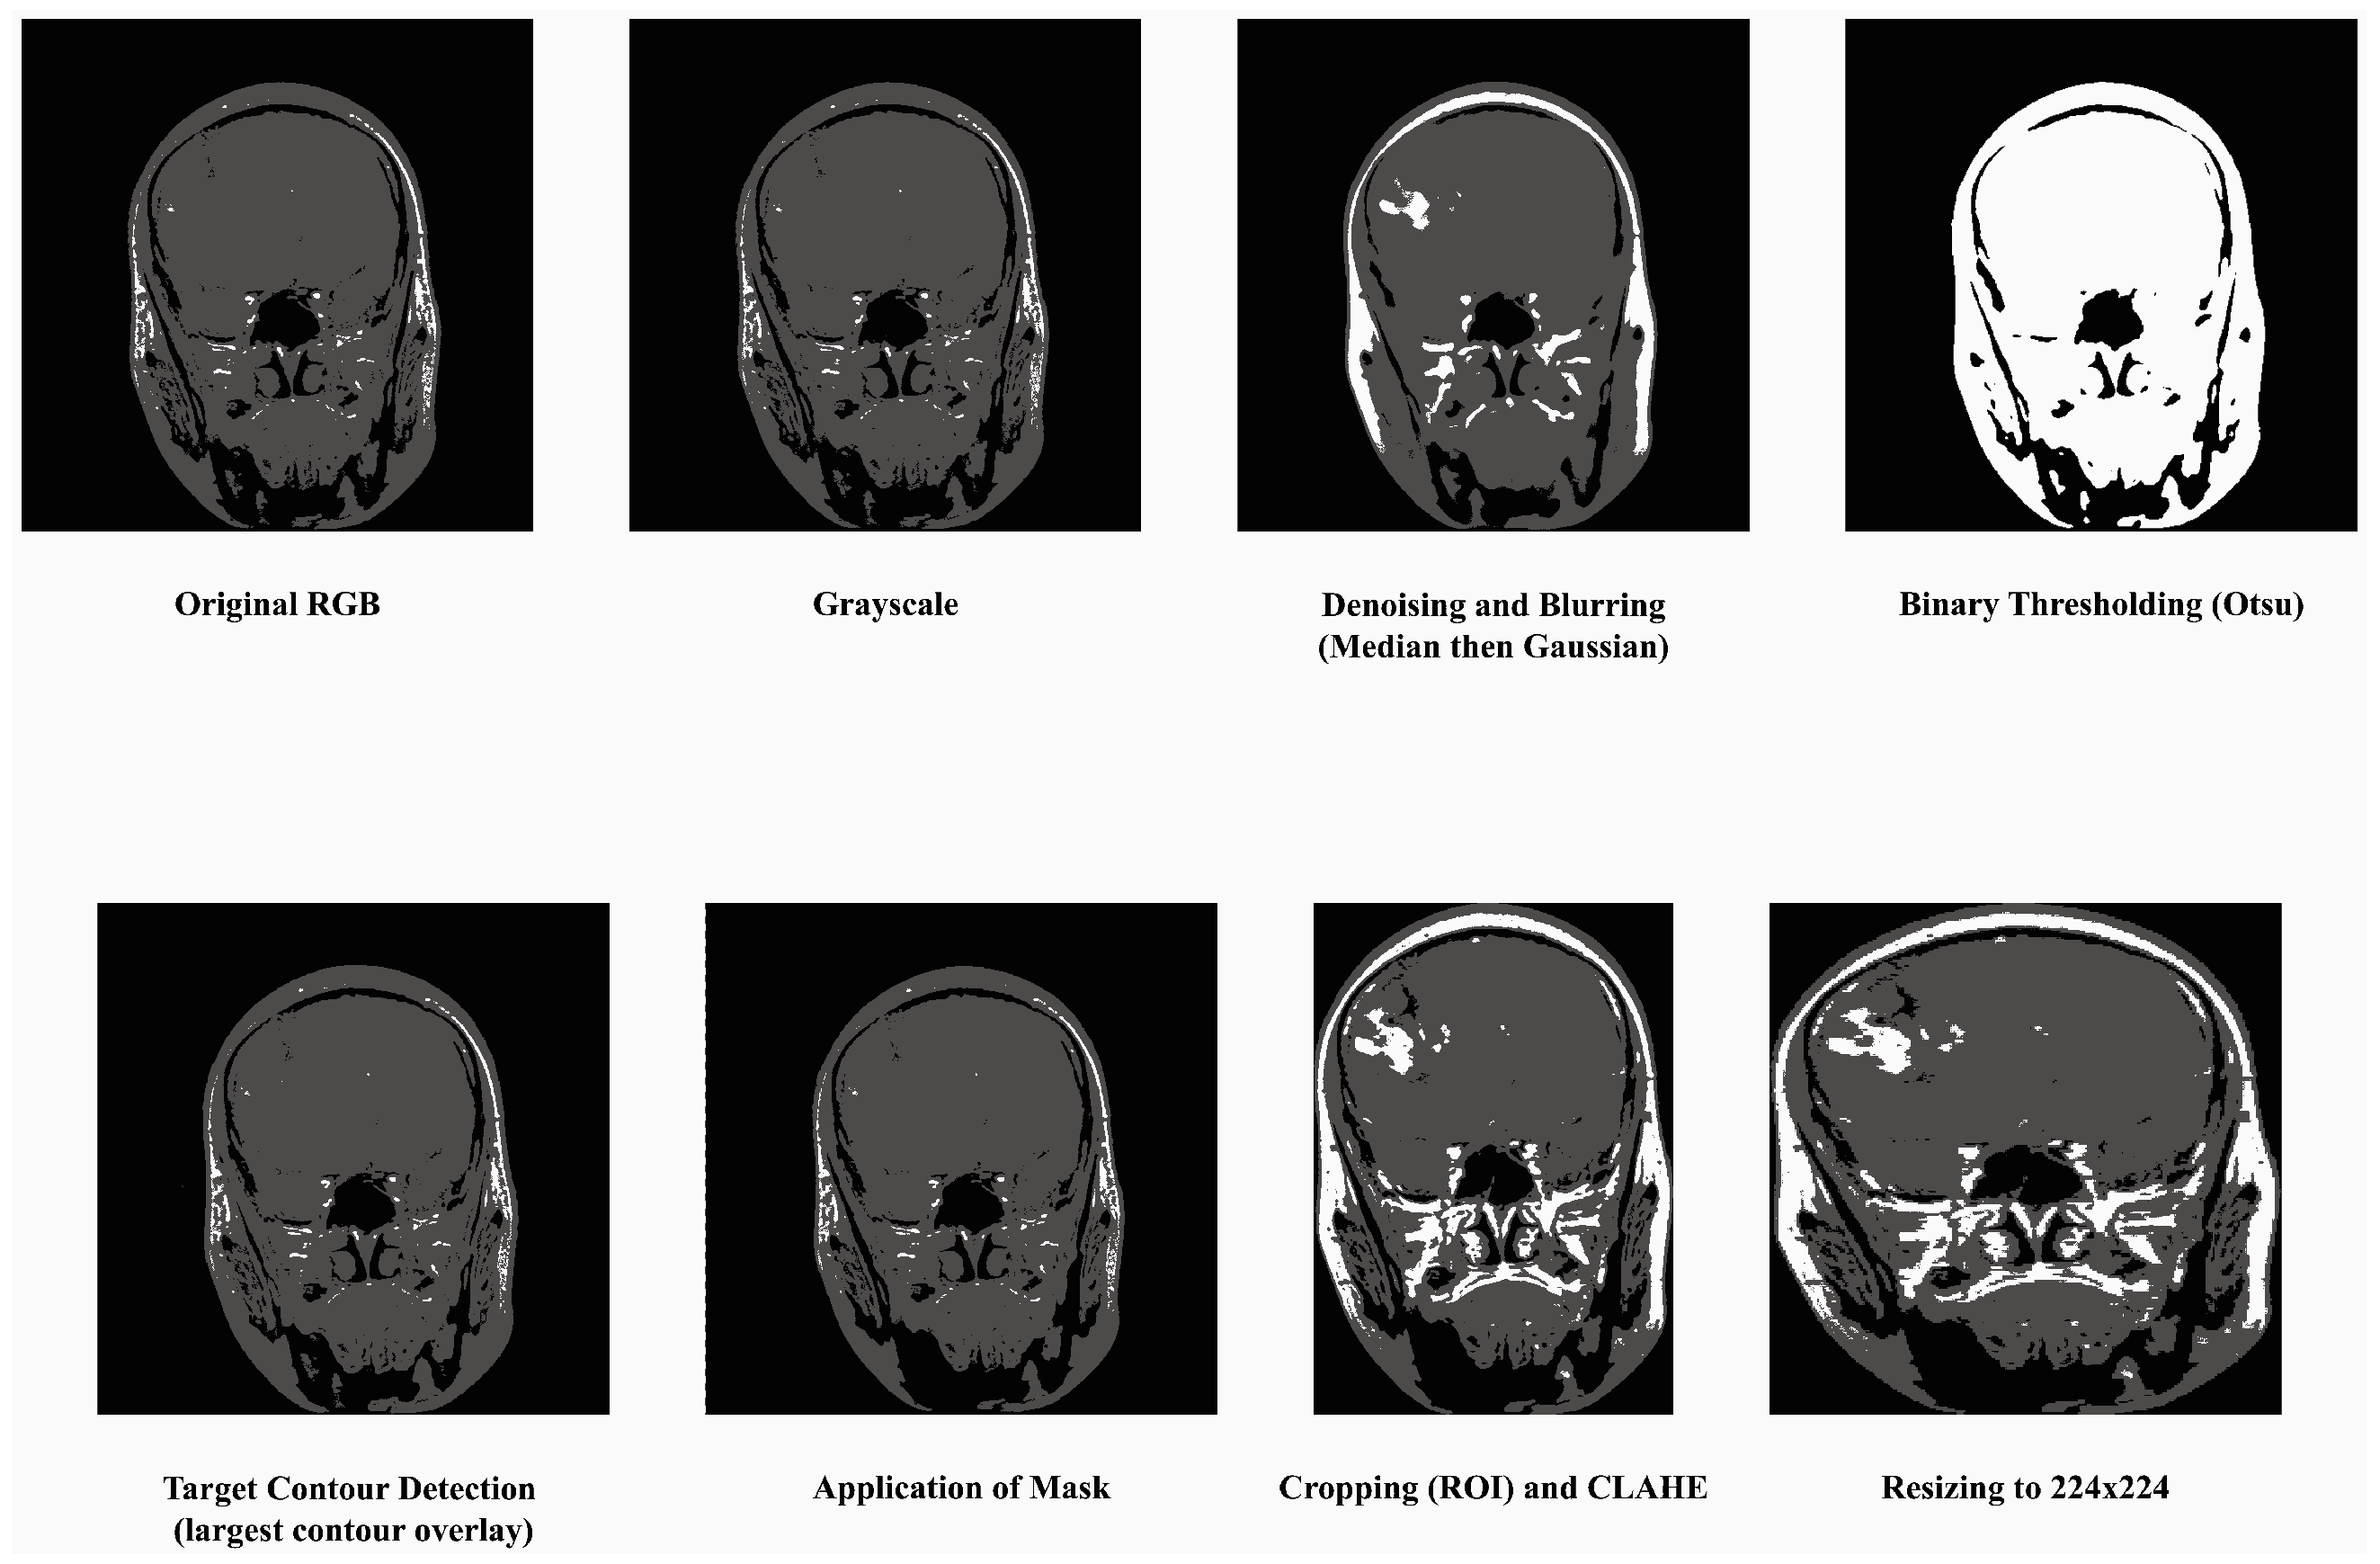

- Convert to Grayscale: Most MRI datasets are in grayscale or captured using only intensity-based information, while some datasets may also include unnecessary color channels (from RGB formats). Converting them to grayscale ensures uniformity in data representation and reduces computation by eliminating redundant information. The process has been done by grayscale using OpenCV’s cv2.cvtColor function. This step also helps focus the model on texture and contrast, which are critical for identifying tumor regions in medical imaging.

- Denoising and Blurring: MRI images often contain artifacts or noise due to acquisition methods, which can obscure key tumor features. Median filtering reduces random noise, preserving the edges and fine details critical for classification without distorting important structures like tumor contours. Blurring is applied to smooth the image and reduce high-frequency variations unrelated to tumors. It helps in suppressing minor unrelated details (e.g., scanner irregularities) and enhances the model’s ability to focus on regional features of tumors rather than noise.

- Binary Thresholding: Binary thresholding creates a clear separation of foreground (possible tumor areas) and background, which aids in isolating the tumor region. By emphasizing areas of interest based on intensity standards, this step generates a mask for tumors, facilitating structured feature extraction and segmentation. The method was applied using a fixed threshold value of 127. This process created a binary mask for tumor region selection. For normalization, pixel intensity ranges were scaled between 0 and 1 prior to thresholding.

- Target Contour Detection: After applying the binary mask, it is essential to extract the tumor region accurately. The contour detection algorithm identifies and segments the largest connected region (potential tumor) and removes non-relevant regions such as background noise or anatomical elements outside the tumor that has been done using findContours function in Python’s OpenCV library. That finds the largest contour by area greater than 500 pixels was selected as the tumor region. This ensures the model focuses on the most relevant part of the image.

- Application of Mask: The binary mask is directly applied to filter out regions irrelevant to the tumor. It allows the model to operate only on imaged regions that likely hold tumor information, improving classification accuracy and computational efficiency.

- Cropping, CLAHE: After isolating the tumor, extracting the region of interest (ROI) eliminates unnecessary background, allowing the model to focus entirely on meaningful features while standardizing input dimensions. This technique enhances the contrast of the tumor region by redistributing brightness in the image, helping highlight subtle details. CLAHE with clip limit = 2.0, grid size = (8 × 8), that reduces the inter-image variability caused by differences in MRI scanner settings, patient anatomy, or lighting conditions, which are particularly important for tumor region detection [48].

- Resizing: To ensure compatibility with the MobileNetV2 architecture, all images are resized to a fixed dimension of 224 × 224 pixels. This step provides uniformity in input size, reduces computational demands, and ensures that the model processes images efficiently without distortion.